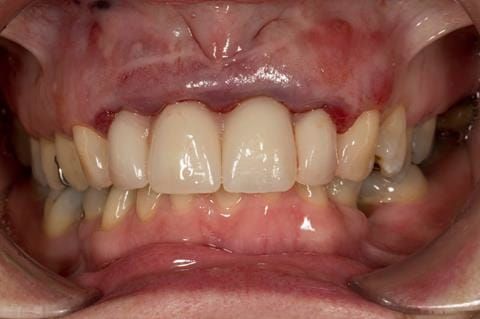

- Extract the upper 2-2 teeth and replace with an interim acrylic based partial denture. Reline the interim denture over 9 - 12 months, replacing with a definitive cobalt chromium based partial denture. The definitive denture would ideally be designed as an occlusal protective splint to reduce the the potential for mechanical wear and breakages of the moderately/heavily restored maxillary dentition. In addition, should further upper teeth require extraction they could be added on to the denture cobalt chromium framework - therefore a new prosthesis would not be required as future teeth are lost. This option would produce an excellent aesthetic outcome. This is the option the patient chose to have.

Following consultation and second discussion appointment the patient chose to have option 3 namely, a maxillary cobalt chromium based partial denture/protective occlusal splint. The clinical situation and treatment process is shown in detail below with photographs. The patient was successfully rehabilitated with this and her quality of life considerably improved. The clinical work was provided by Finlay and the technical work by Rowan.